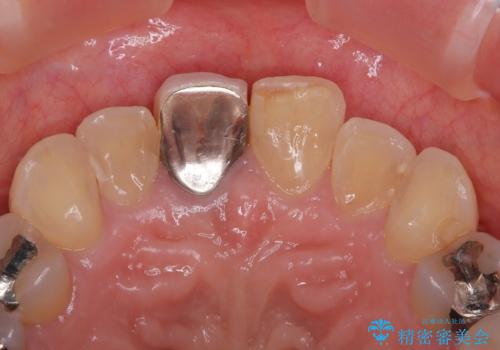

- 保険診療で装着した前歯のクラウンが変色して気になってきたとのことで来院された患者様です。

歯肉退縮による歯肉ラインの黒い縁も気になってきたとのことで、オールセラミッククラウンにて補綴治療を行うこととしました。